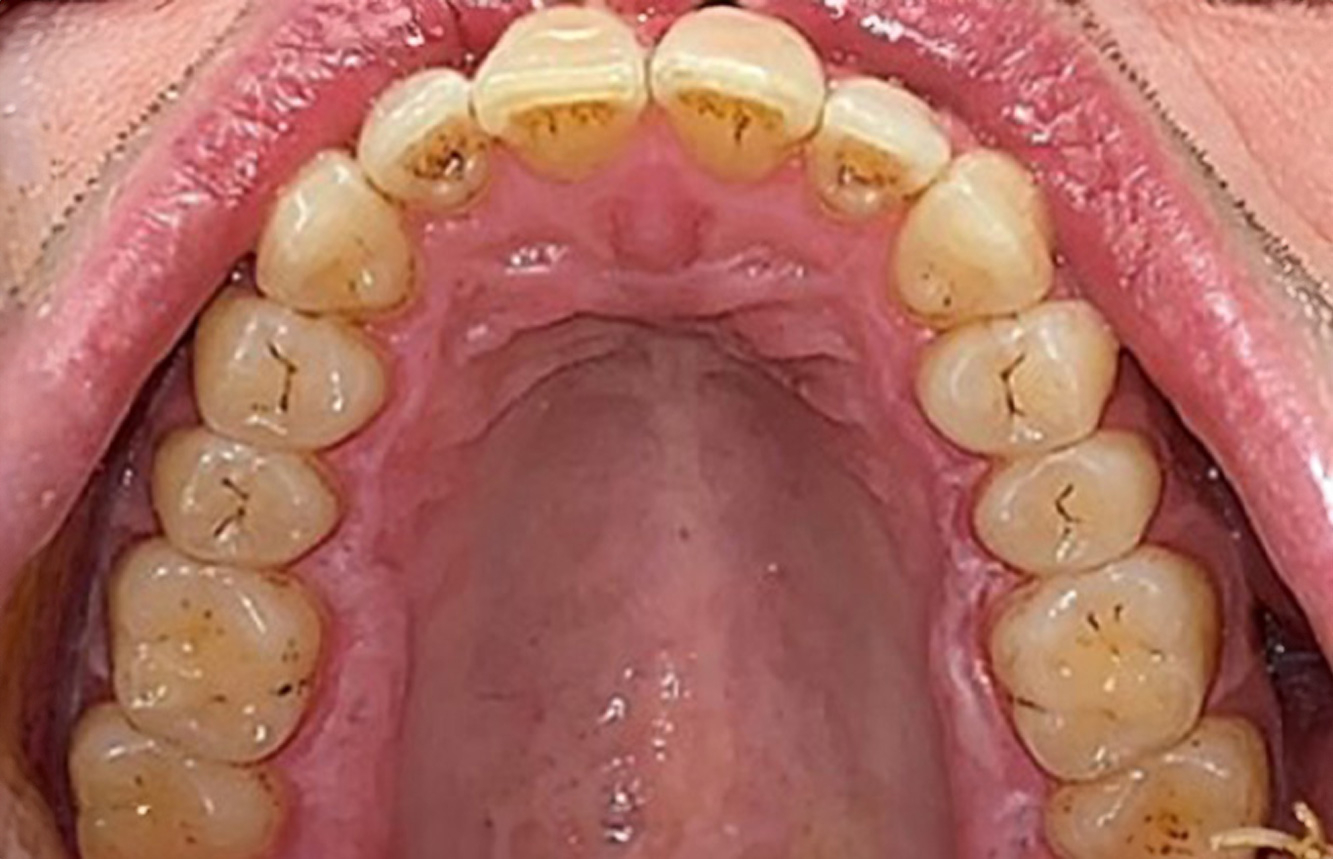

The healthy patient with pre-existing periodontal disease & peri-implantitis

Paciente sana con enfermedad periodontal previa

La paciente de 68 años no tiene enfermedades previas relevantes de la salud general ni toma medicación; sus hábitos alimentarios tampoco suponen un riesgo especial. La paciente tiene dos implantes (tercer cuadrante, desde hace cinco años) y una enfermedad previa periodontal (periodontitis en etapa IV, grado B) con pérdida dental. Actualmente las condiciones periodontales son estables, pero la periodontitis aumenta de manera determinante las complicaciones biológicas cuando se realizan implantes y puede ocasionar la pérdida de un implante (21). Para la sesión de profilaxis se hacen cuatro recomendaciones. más información